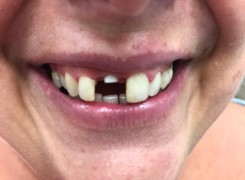

Pan Ryszard trafił do Naszego Gabinetu z jasno sprecyzowanym oczekiwaniem. Miał 84 lata i chciał odzyskać możliwość swobodnego spożywania posiłków oraz poprawienia sobie komfortu życia a także prosił aby przywrócić mu piękny uśmiech jakim cieszył się przed laty. Już na początku pierwszej rozmowy zastrzegł, że interesuje go wyłączenie rozwiązanie uzupełnieniem protetycznym stałym. Nie miał zamiaru użytkować żadnych protez ruchomych. Mając na uwadze powyższe wykonaliśmy Panu Ryszardowi zdjęcie pantomograficzne oraz badanie tomograficzne szczęki i żuchwy na postawie których zapanowywaliśmy Pacjentowi optymalne rozwiązanie – stałe uzupełnienie protetyczne w postaci 28 koron cyrkonowych zamontowanych do dwóch belek cyrkonowych które będą przymocowane do 16 implantów w konfiguracji 8 wszczepów w szczęcie 8 w żuchwie. Po omówieniu powyższego planu przystąpiliśmy do Wspólnej pracy której efekty w poszczególnych etapach prezentujemy poniżej.